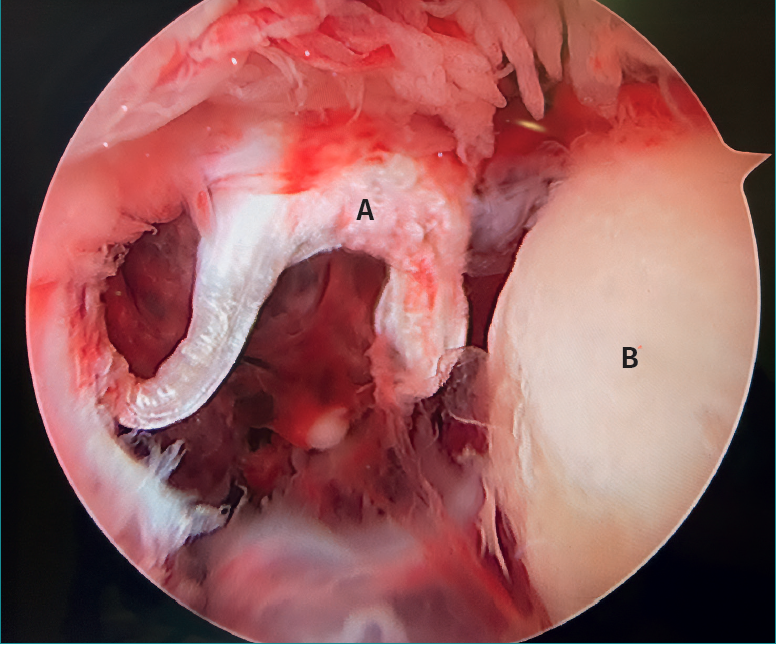

The letter pi on the ankle

- The letter pi on the ankle